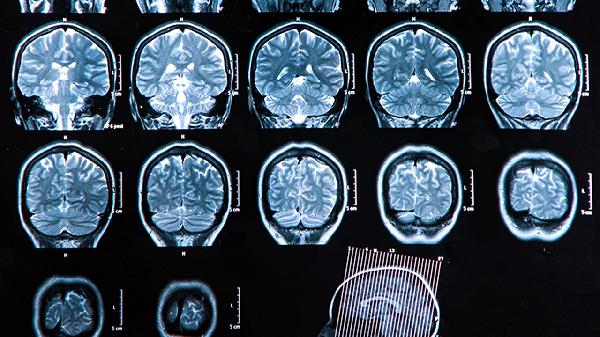

中枢神经系统囊虫病可分为脑实质型、脑室型、蛛网膜下腔型和混合型四种类型。

混合型指同时存在两种以上寄生类型的复杂情况。临床表现多样且严重,可能同时出现癫痫、脑积水、脑膜炎等多种症状。影像学检查可见多部位病灶共存。治疗需根据主要病变部位制定个体化方案,通常需要药物与手术联合干预。